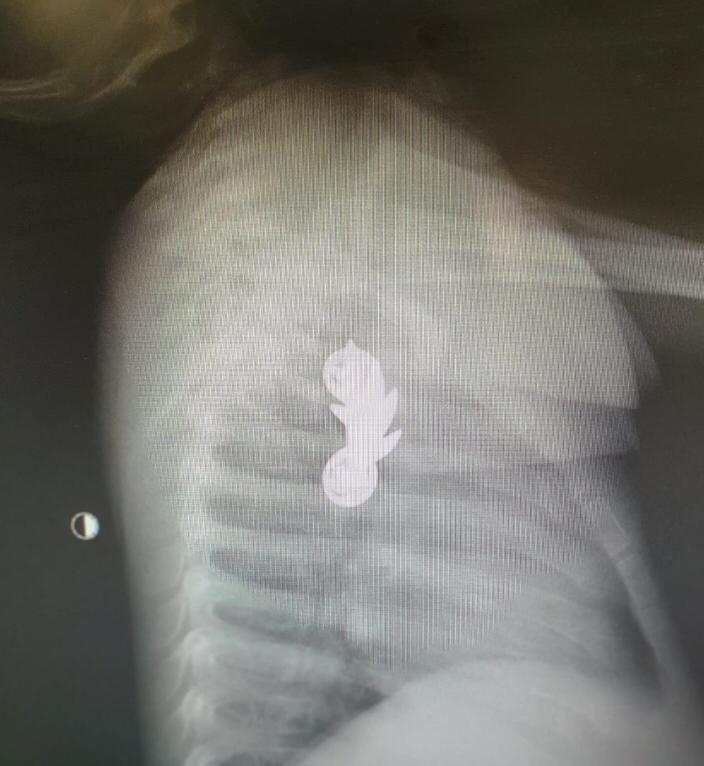

המציאות במקרה זה עלתה על כל דמיון – בצילום נצפה חפץ שזוהה כסיכת מ"מ צה"לית. עקב גודלו וצורתו החריגים של הגוף הזר הוזעק צוות משולב של מומחי גסטרו ילדים, אף אוזן גרון וטיפול נמרץ ילדים לבית החולים והתינוק הוכנס מידית לחדר הניתוח.

ד"ר מיכל קורי, רופאה מומחית לגסטרואנטרולוגיה ילדים בקפלן, יחד עם מומחה אף אוזן וגרון, ד"ר מאיר וורמן, שלפו בהצלחה את סיכת המ"מ בשלמותה בפעולה ממושכת. "כאשר נתגלתה סיכת המ"מ בצילום היה ברור שהפרוצדורה תהיה מאוד מורכבת בשל הגודל והחדות של הגוף הזר", היא מתארת. "הצוות הרפואי שכלל מומחים מתחום גסטרו ילדים, אף אוזן גרון וטיפול נמרץ ילדים, החליט על ביצוע גסטרוסקופיה בהרדמה כללית להוצאת הגוף הזר. בעזרת הצינור הועלתה הסיכה בעדינות מהוושט האמצעי לחלל הפארינקס, ובשלב השני ד"ר ורמן שלף את הסיכה בשלמותה" , היא תארה. "העובדה שסיכת המ"מ הוצאה בזמן מנעה סיכונים שעלולים להיגרם במקרים אלו כגון קרע של הושט, זיהום וקשיי בליעה. אין ספק שערנות ההורים במקרה זה הייתה בעלת חשיבות רבה".